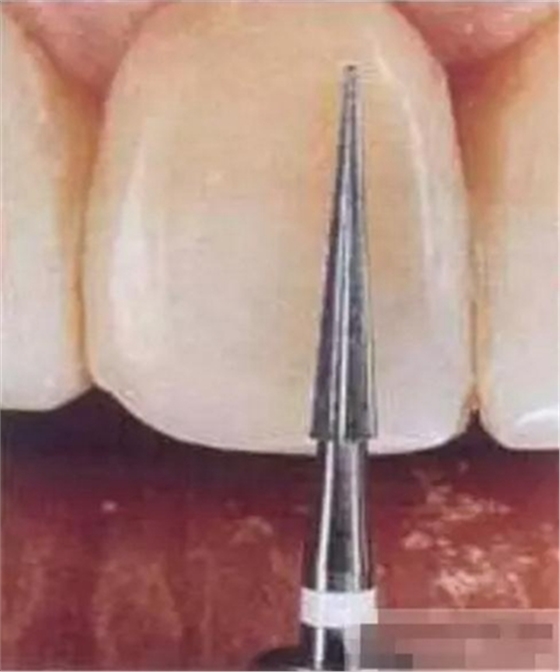

選擇合適的完成鉆制備根管,

通常深入到根管的1/2至2/3處

在使用根管纖維樁時(shí)根管預(yù)備的深度應(yīng)該是多少呢?

在回答這個(gè)問(wèn)題前,首先應(yīng)該了解根管內(nèi)的粘接狀況。最佳的粘接效果發(fā)生于根管的冠1/3和中1/3。由于根1/3的牙本質(zhì)小管往往不能充分敞開(kāi),此區(qū)域幾乎沒(méi)有粘接作用發(fā)生,所以,根管纖維樁放置的深度無(wú)需超過(guò)根中1/3。同樣重要的是,根管預(yù)備時(shí)鉆的速度不要過(guò)快,防止飛濺的牙膠粘在根管內(nèi)壁上。所以,根管壁的清理也很重要,以確保牙本質(zhì)小管充分開(kāi)放。Dr.Vanini使用噴砂和酸蝕來(lái)充分清理根管壁和窩洞。研究顯示,粘接劑的作用也很重要,粘接根管纖維樁要求使用滲透力強(qiáng)粘結(jié)作用好的粘接劑。